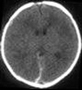

Hematoma subdural

Esta diapositiva nos muestra un caso típico de lesión neurológica, especificamente un hematoma subdural representado en una imagen de Tomografía axial computarizada (TAC).